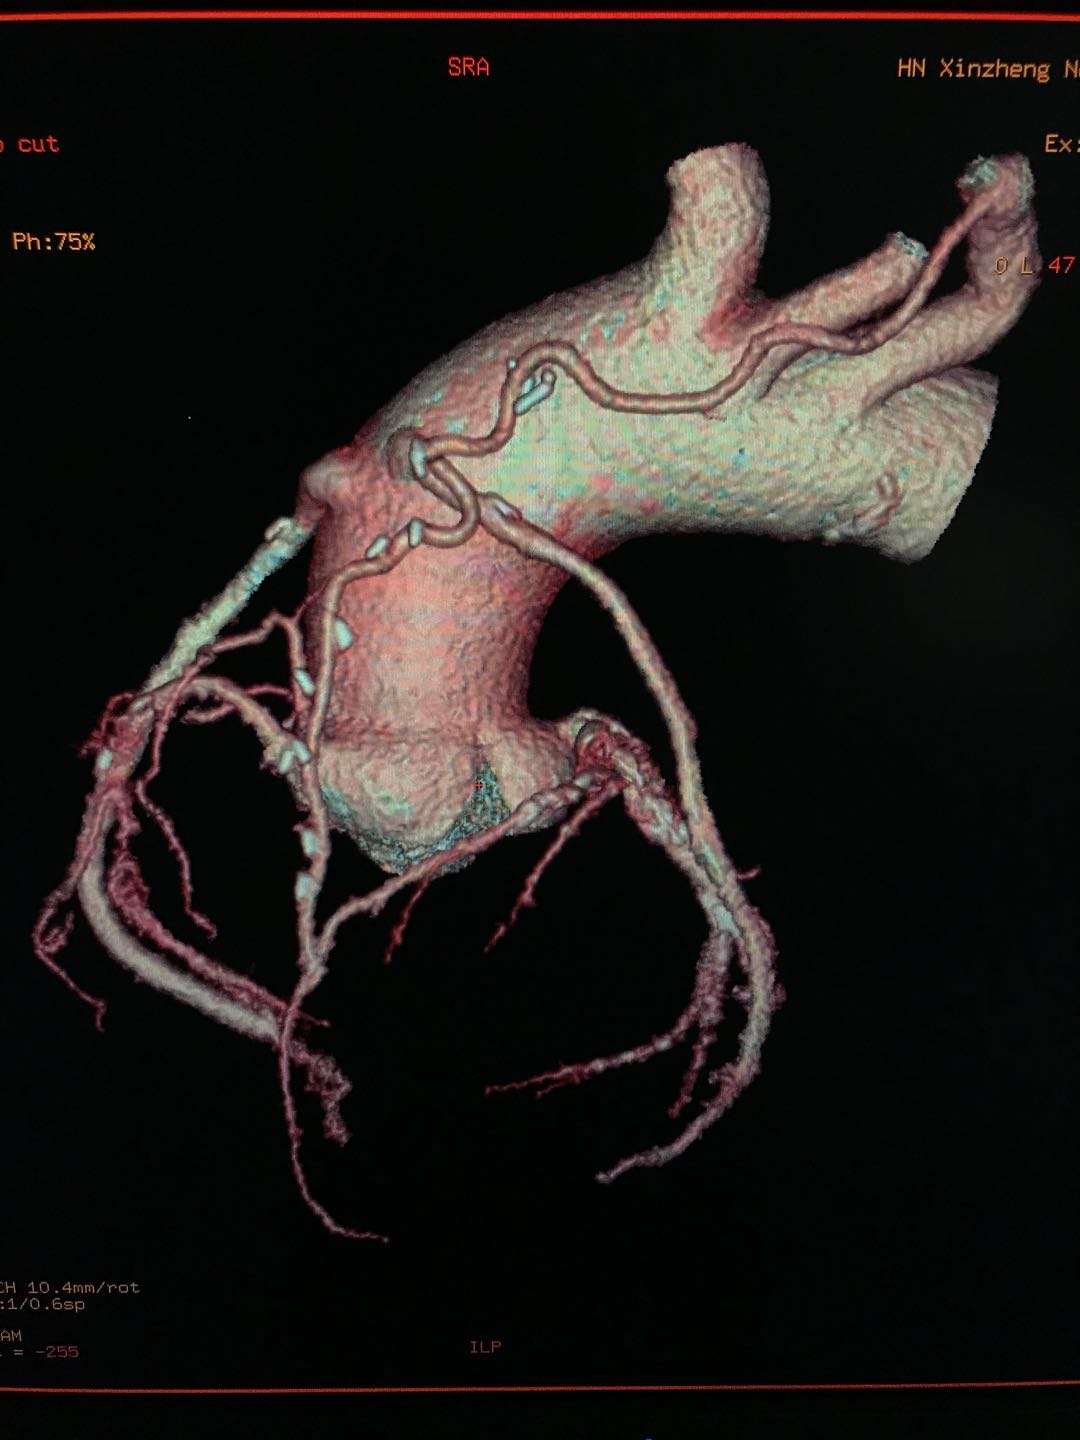

要想排除冠心病诊断,首选冠脉CTA 冠脉CTA检查,是一种特殊的增强CT扫描,只要图像清晰,诊断无误,排除冠心病诊断的准确率高达99%。除此以外,目前其他任何的心脏检查均不能排除冠心病的诊断。

冠脉支架植入术后或搭桥术后的复查

以往支架植入术后的复查需要再次做造影复查。现在应用冠脉CTA复查,简单方便。